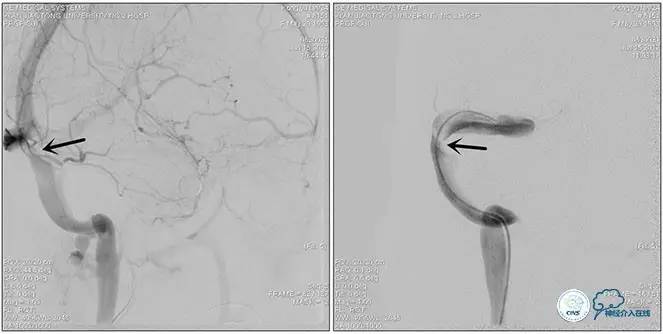

手术方案

1、6mm×20mmAviator球囊(Cordis)分段对狭窄部位进行扩张。

2、植入7mm×40mmPrecise自膨支架。

术后造影

术毕远近端压力差为:0